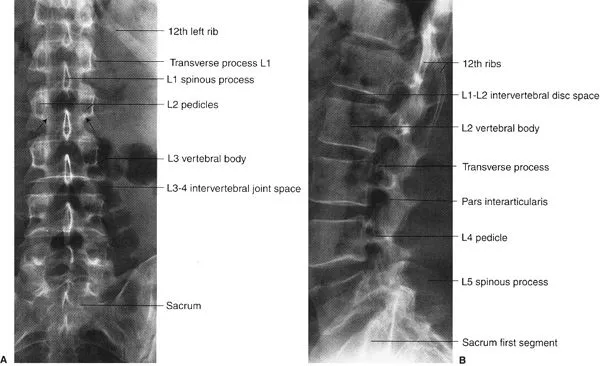

Lumbosacral Spine - Low-Back Locator

Key palpable and radiological landmarks for safe procedural access and diagnosis in the lower back region.